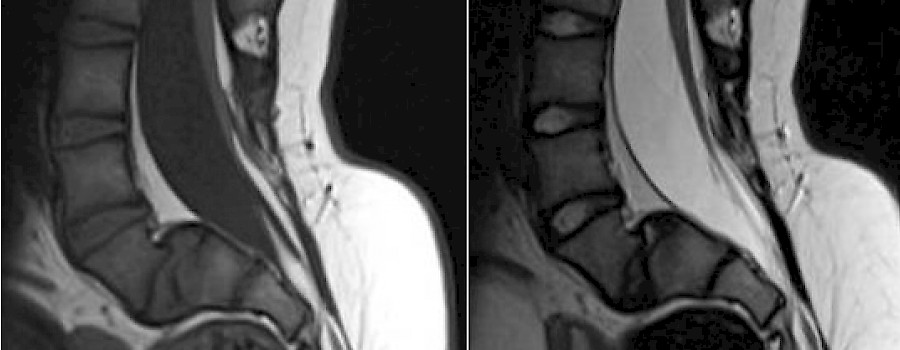

Bei der Magnetresonanztomographie handelt es sich um ein Schnittbildverfahren, welches auf dem sogenannten Resonanzphänomen basiert. Die Grundlagenforschungen auf diesem Gebiet wurden von Felix Bloch und Edward Purcell durchgeführt. (1952 Nobelpreis für Physik).